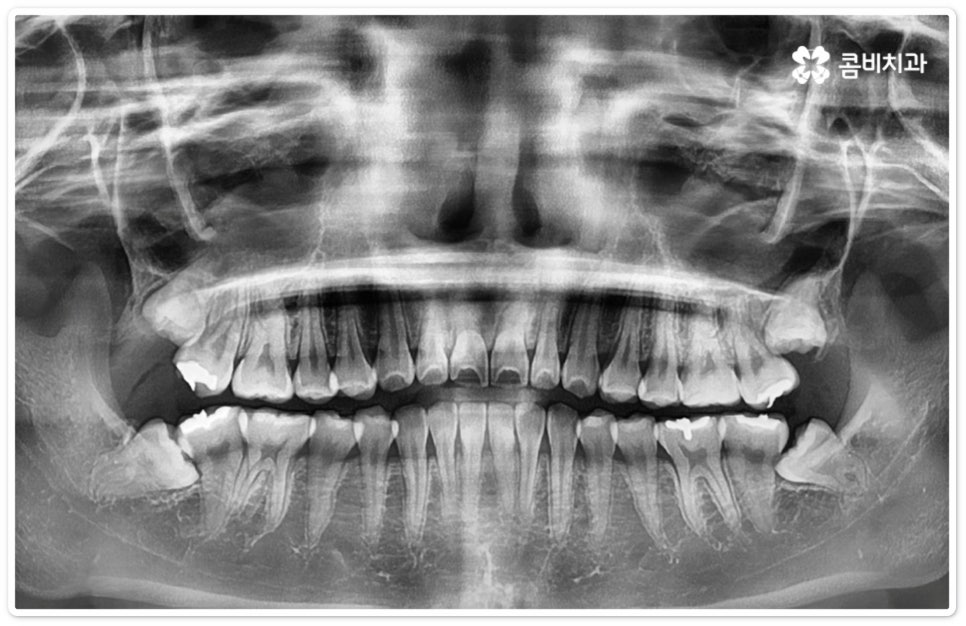

사랑니의 개수, 위치, 각도나 뿌리의 형태, 매복 깊이 등은 사람마다 다른데 그 중에서 특히 완전히 매복된 상태로 비스듬히 누운 채 자리잡은 아래 사랑니의 경우 턱을 가로지르는 하치조 신경과 가깝기 때문에 누운사랑니발치 시 신중을 기하지 않으면 혹시 모를 부작용인 감각 이상을 초래할 수 있으므로 뛰어난 해부학적 지식과 풍부한 임상 경험, 세심한 기술력을 가지고 있는 숙련된 의료진에게 치료를 받으시길 권유드리고 있어요. 혹시라도 신경 손상이 발생하게 되면 입술이나 턱이 마취된 듯 침이 흘러도 감각이 없거나 양치질을 할 때 물이 입술밖으로 세어나가는 상태가 유발될 수 있으니 조심해야 할 거예요.

우리나라 사람 중에 약 7% 정도는 사랑니가 아예 없다고 하지만 보통 25세가 지났는데 사랑니가 나오지 않았다면 매복 사랑니이거나 누워있는 사랑니인 경우가 많으므로 정밀 검진을 받아보실 필요가 있는데요. 이때 염증을 지속적으로 유발하거나 음식물이 끼면서 관리가 잘 안 되면서 발생하는 충치 등 좋지 않은 영향을 주고 있다면 발치 처치를 해 주는 게 좋은데, 20대에 누운사랑니발치 를 진행하는 것이 40대 이후에 하는 것보다 통증 및 출혈도 덜하고 회복도 빠를 수 있으니 이를 염두에 두시길 바라고 있어요.

특히 40세 이상 성인분들의 경우 치아의 긴 뿌리가 완전하게 형성이 되어 있어 치근 유착이 심한 케이스가 있을 수 있으며 대부분 연령이 증가할수록 사랑니 주위 뼈가 단단해지고 탄력성이 감소하는 경향을 보이기 때문에 상황에 따라 무리하게 매복된 뿌리까지 발치할 경우 턱뼈가 부러지거나 신경이 손상되는 등의 합병증 위험이 증가하는 케이스에서는 치아 뿌리는 남긴 채 사랑니의 머리 부분만 잘라서 빼내는 치관절제술을 시행해야 할 수도 있는데요. 이런 경우 약 14%81%는 치관절제술 후 치아 뿌리가 상방으로 움직여서 잇몸 밖으로 노출이 되기 때문에 다시 치근을 제거하는 수술을 해주게 되는데, 환자분들의 입장에서는 수술을 두 번에 걸쳐 하기 때문에 거부감이 들 수 있으나 하치조 신경과의 거리를 벌린 후 완전히 제거하는 것이 통증 및 감염의 위험을 줄이는 보다 안전한 방법이므로 치관절제술 후 1달1년 정도의 시간을 두고 3D CT 촬영을 통해 다시 위치를 꼼꼼하게 확인한 후 치료 받으시길 권유드리고 있어요.

매복 형태의 사랑니는 잇몸을 절개하고 발치해야 하며, 특히 깊숙하게 누운사랑니발치 시에는 신경을 건드리지 않도록 사랑니를 조각내어 조심해서 빼내야 할 뿐 아니라 환자분들의 상태에 따라 잇몸뼈를 조금씩 삭제해야 할 수도 있기 때문에 이러한 고난도 시술에는 주변 조직의 손상을 최소화하고 혹시 모를 부작용의 위험을 줄이며 출혈 및 통증이 커지지 않도록 하기 위해서 시술자의 높은 숙련도가 더욱 요구된다고 할 수 있어요. 또한 매복된 사랑니의 각도, 뿌리 형태, 인접 치아와의 관계, 신경 위치 등을 정확하게 파악하고 체계적인 맞춤 계획을 세워 무리하지 않게 사랑니 발치 수술을 진행하기 위해서 정밀 진단이 가능한 3D CT 장비가 있는 치과에서 꼼꼼한 검사부터 받아보는 것이 중요할 거예요.